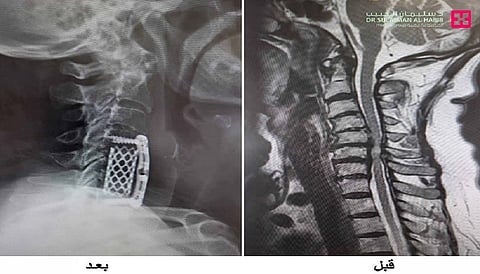

ذكر ذلك الدكتور عبدالله النبهان استشاري جراحة المخ والأعصاب والعمود الفقري رئيس الفريق الطبي المعالج، والذي أضاف أن المراجعة وصلت المستشفى على كرسي متحرك وهي تشكو من آلام حادة، وتم إخضاعها لفحوصات طبية دقيقة بالأشعة المقطعية C.T.Scan والرنين المغناطيسي M.R.I، وتبين من الفحوصات أن لديها انزلاقات غضروفية، وضغطًا شديدًا على النخاع الشوكي من الفقرة الرابعة حتى السابعة من الفقرات العنقية، وضيقًا شديدًا في القناة الشوكية، وهو ما أدى إلى حدوث ضمور في النخاع الشوكي؛ مما سبب تلك الأعراض مع فقدان التوازن عند محاولة الوقوف، وحدوث تنميل حاد في جميع الأطراف وصولًا للعمود الفقري، وكذلك "فقدان الاتزان والقدرة على الحركة والمشي. كما تبين من تاريخها المرضى إصابتها بالسكر والضغط.

وأوضح د.النبهان أنه بعد دراسة الحالة، تَقرر إجراء التدخل الجراحي؛ إذ أجريت لها عملية استغرقت 4 ساعات، وتم فيها استئصال فقرتين مع الغضاريف المجاورة واستبدالهما بفقرات صناعية لإزالة الضغط الحاد على الأعصاب، ووضع مسامير لتثبيت فقرات العمود الفقري، بالإضافة إلى تثبيت الفقرات بصحيفة ومسامير، مع استخدام تقنيات الميكروسكوب الجراحي المتطور والملاحة العصبية Pentero Microscope، وتحرير الحبل الشوكي وإزالة الضغط بالفقرات.